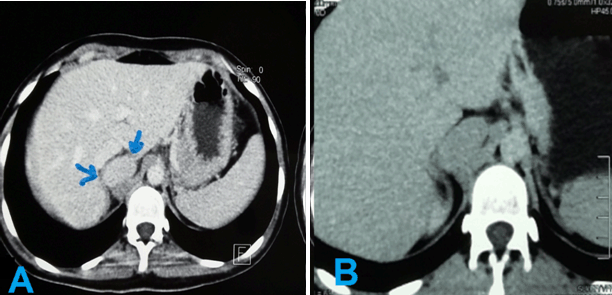

An abdominal ultrasound was performed and showed a 4.5x3 cm mass (Figure 1), which was confirmed on abdominal computed tomography (CT) scan. Abdominal pelvic multi slice CT scan before and after contrast in sagittal and coronal sections demonstrated that the mass was retro caval adjacent to the right adrenal gland (Figure 2) (Figure 3) (Figure 4).

The mass was oval, well defined, homogeneous without fatty components and no calcification or necrosis. The mass was high density (35 HU) before contrast and clearly homogeneously enhancing mass in arterial time.

Figure 2: Abdominal axial multi-slice computed tomography scan at arterial phase, (A) Venous phase, (B) Showing a retro caval mass at the region of right adrenal gland.

Figure 3: (A) Abdominal axial multi-slice computed tomography reveals an oval ,well-defined and homogeneous mass which is located above right renal region , no calcifications or necrosis, and (B) abdominal coronal multi-slice computed tomography with contrast (arterial phase) reveals the above mass uptaking contrast homogeneously.